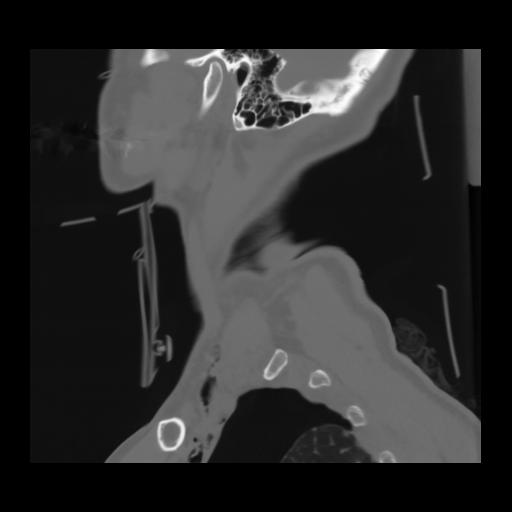

14 P.BLANDAS,,Sagittal,2.000,P.BLANDAS,Sagittal,